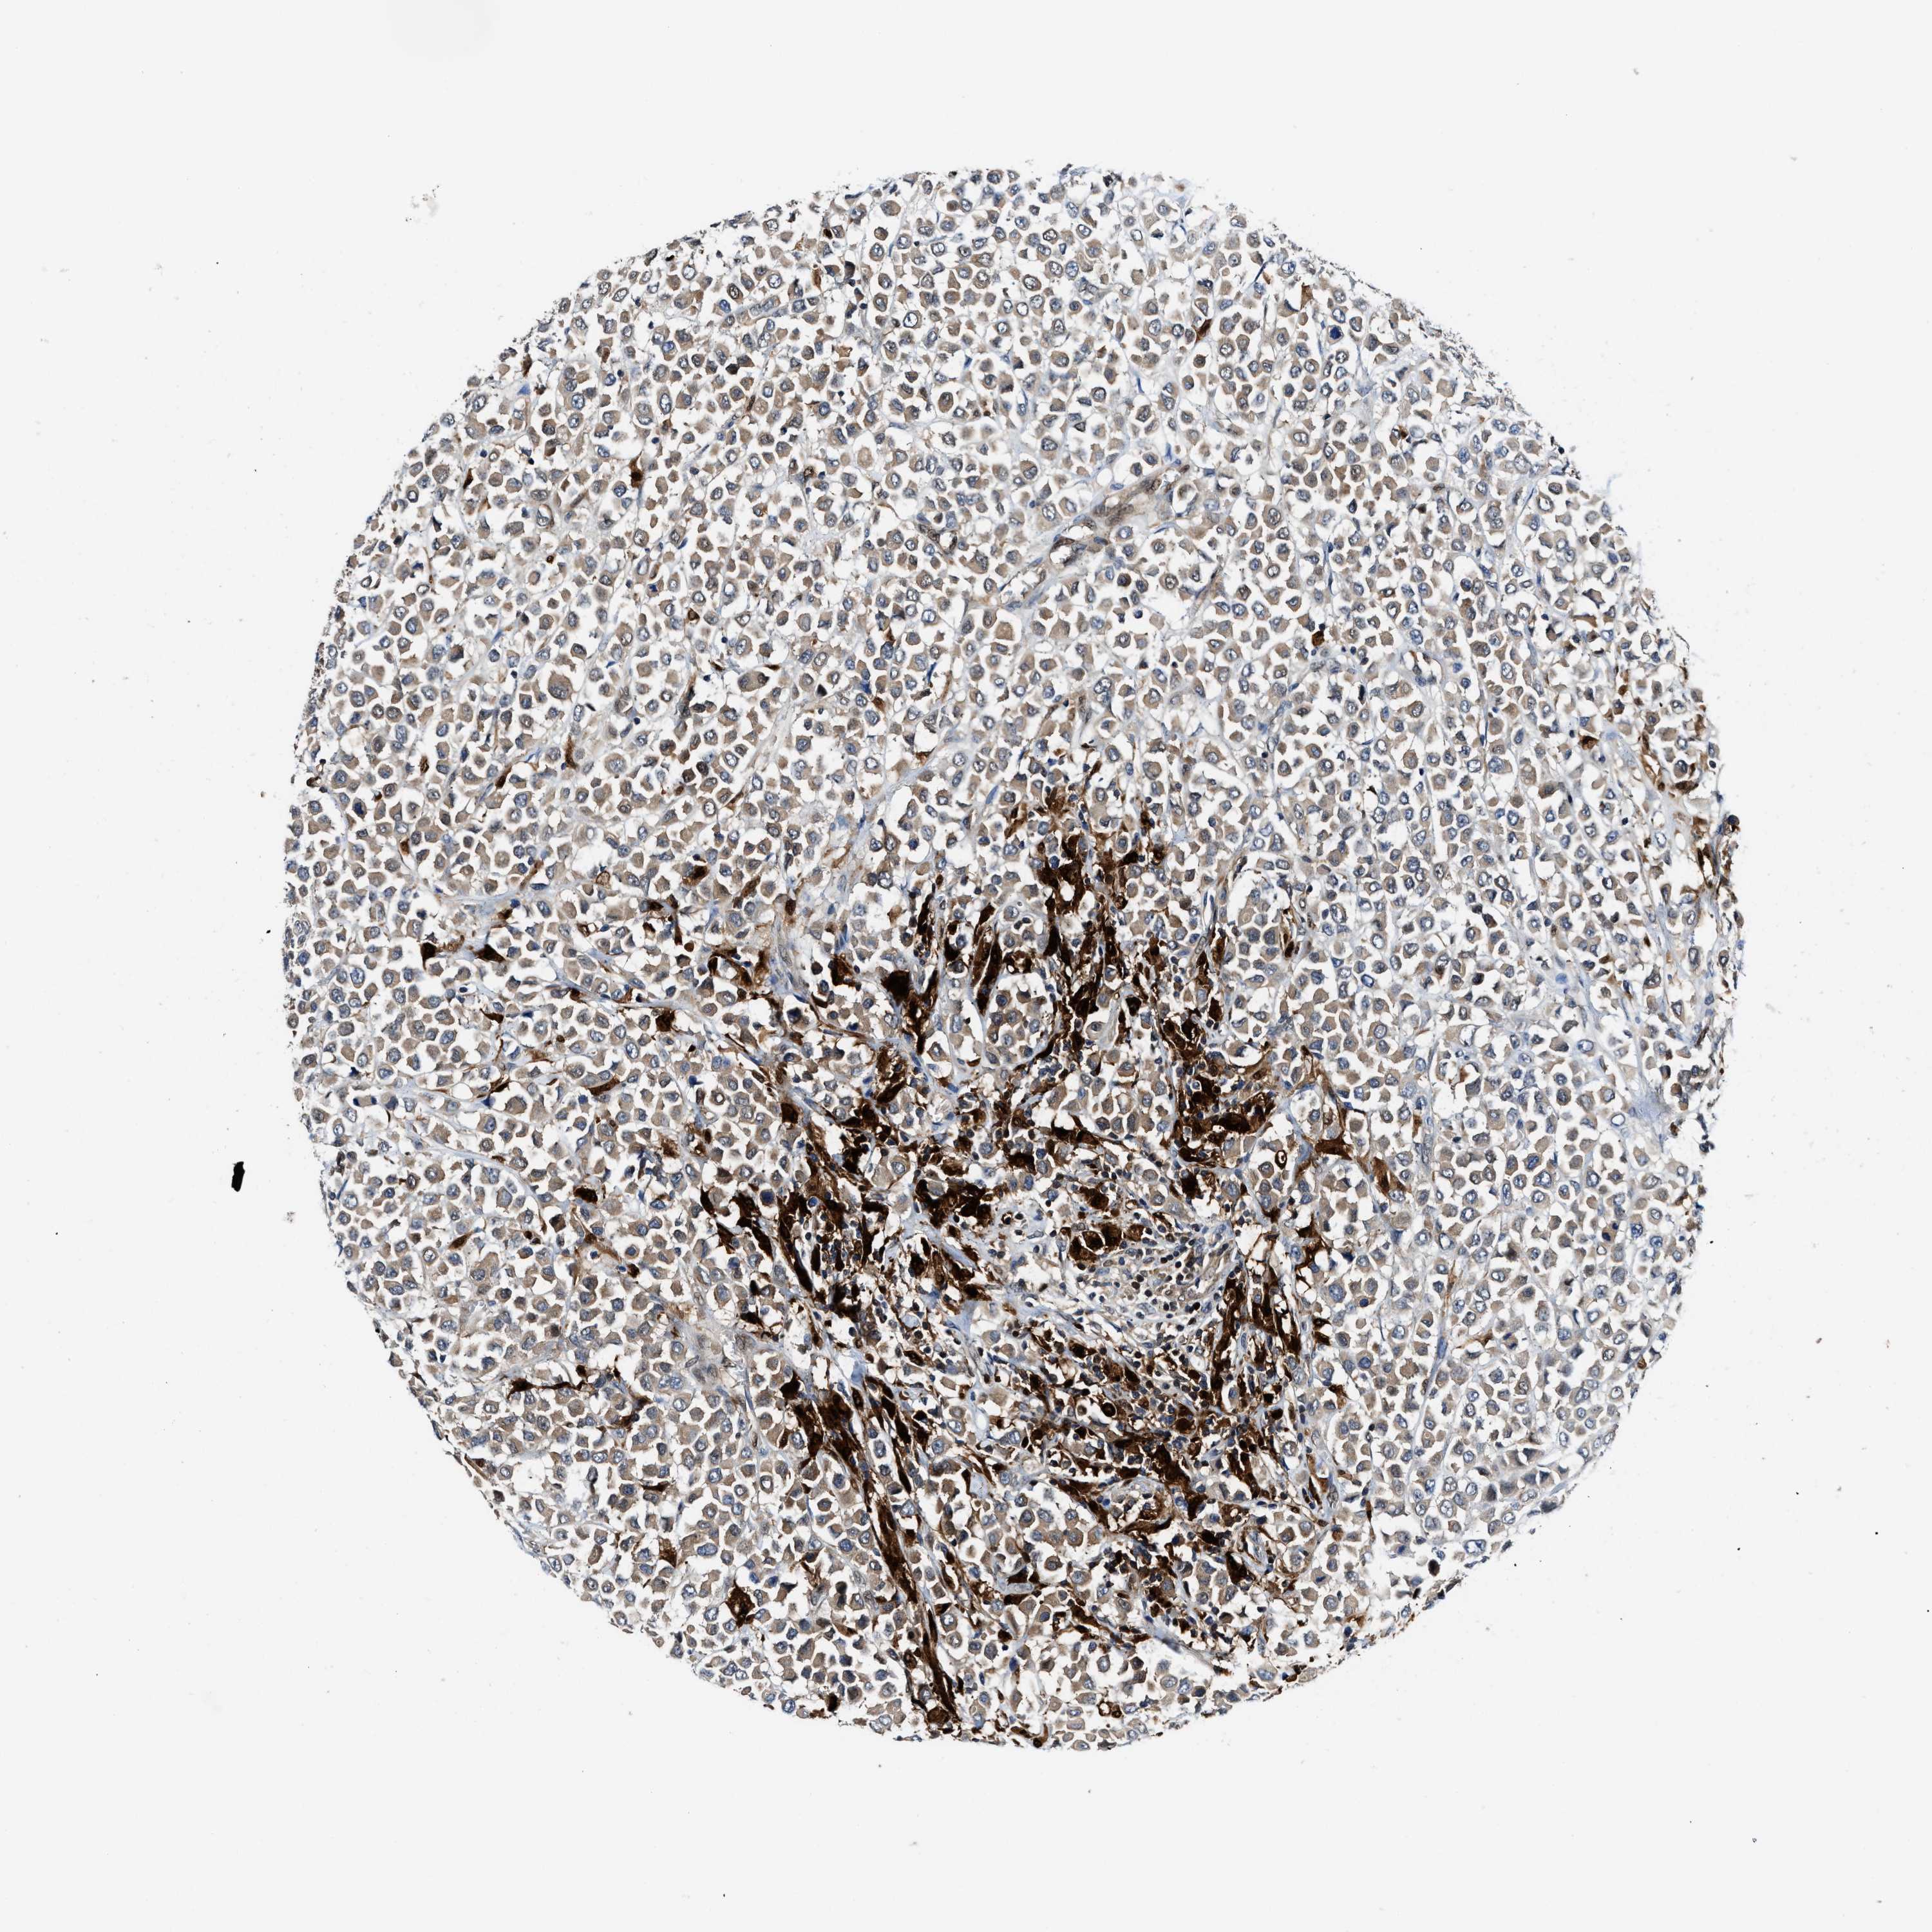

CANCER BREAST CANCER Show tissue menu

BRCA TCGA BRCA VALIDATION PROTEIN EXPRESSION

Breast cancer

Human cancer

Breast invasive carcinoma